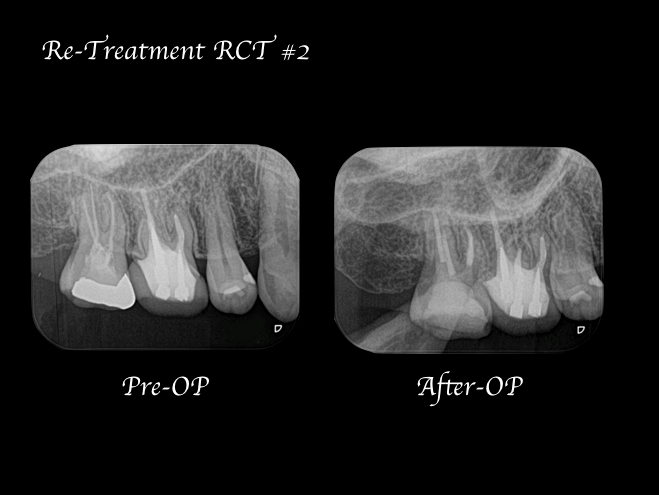

【症例】再根管治療| CT、マイクロスコープを使った精密根管治療

治療内容 再根管治療|精密根管治療

治療期間 1週間

治療回数 2回

治療費用 154,000円(税込)

※処置当時の料金